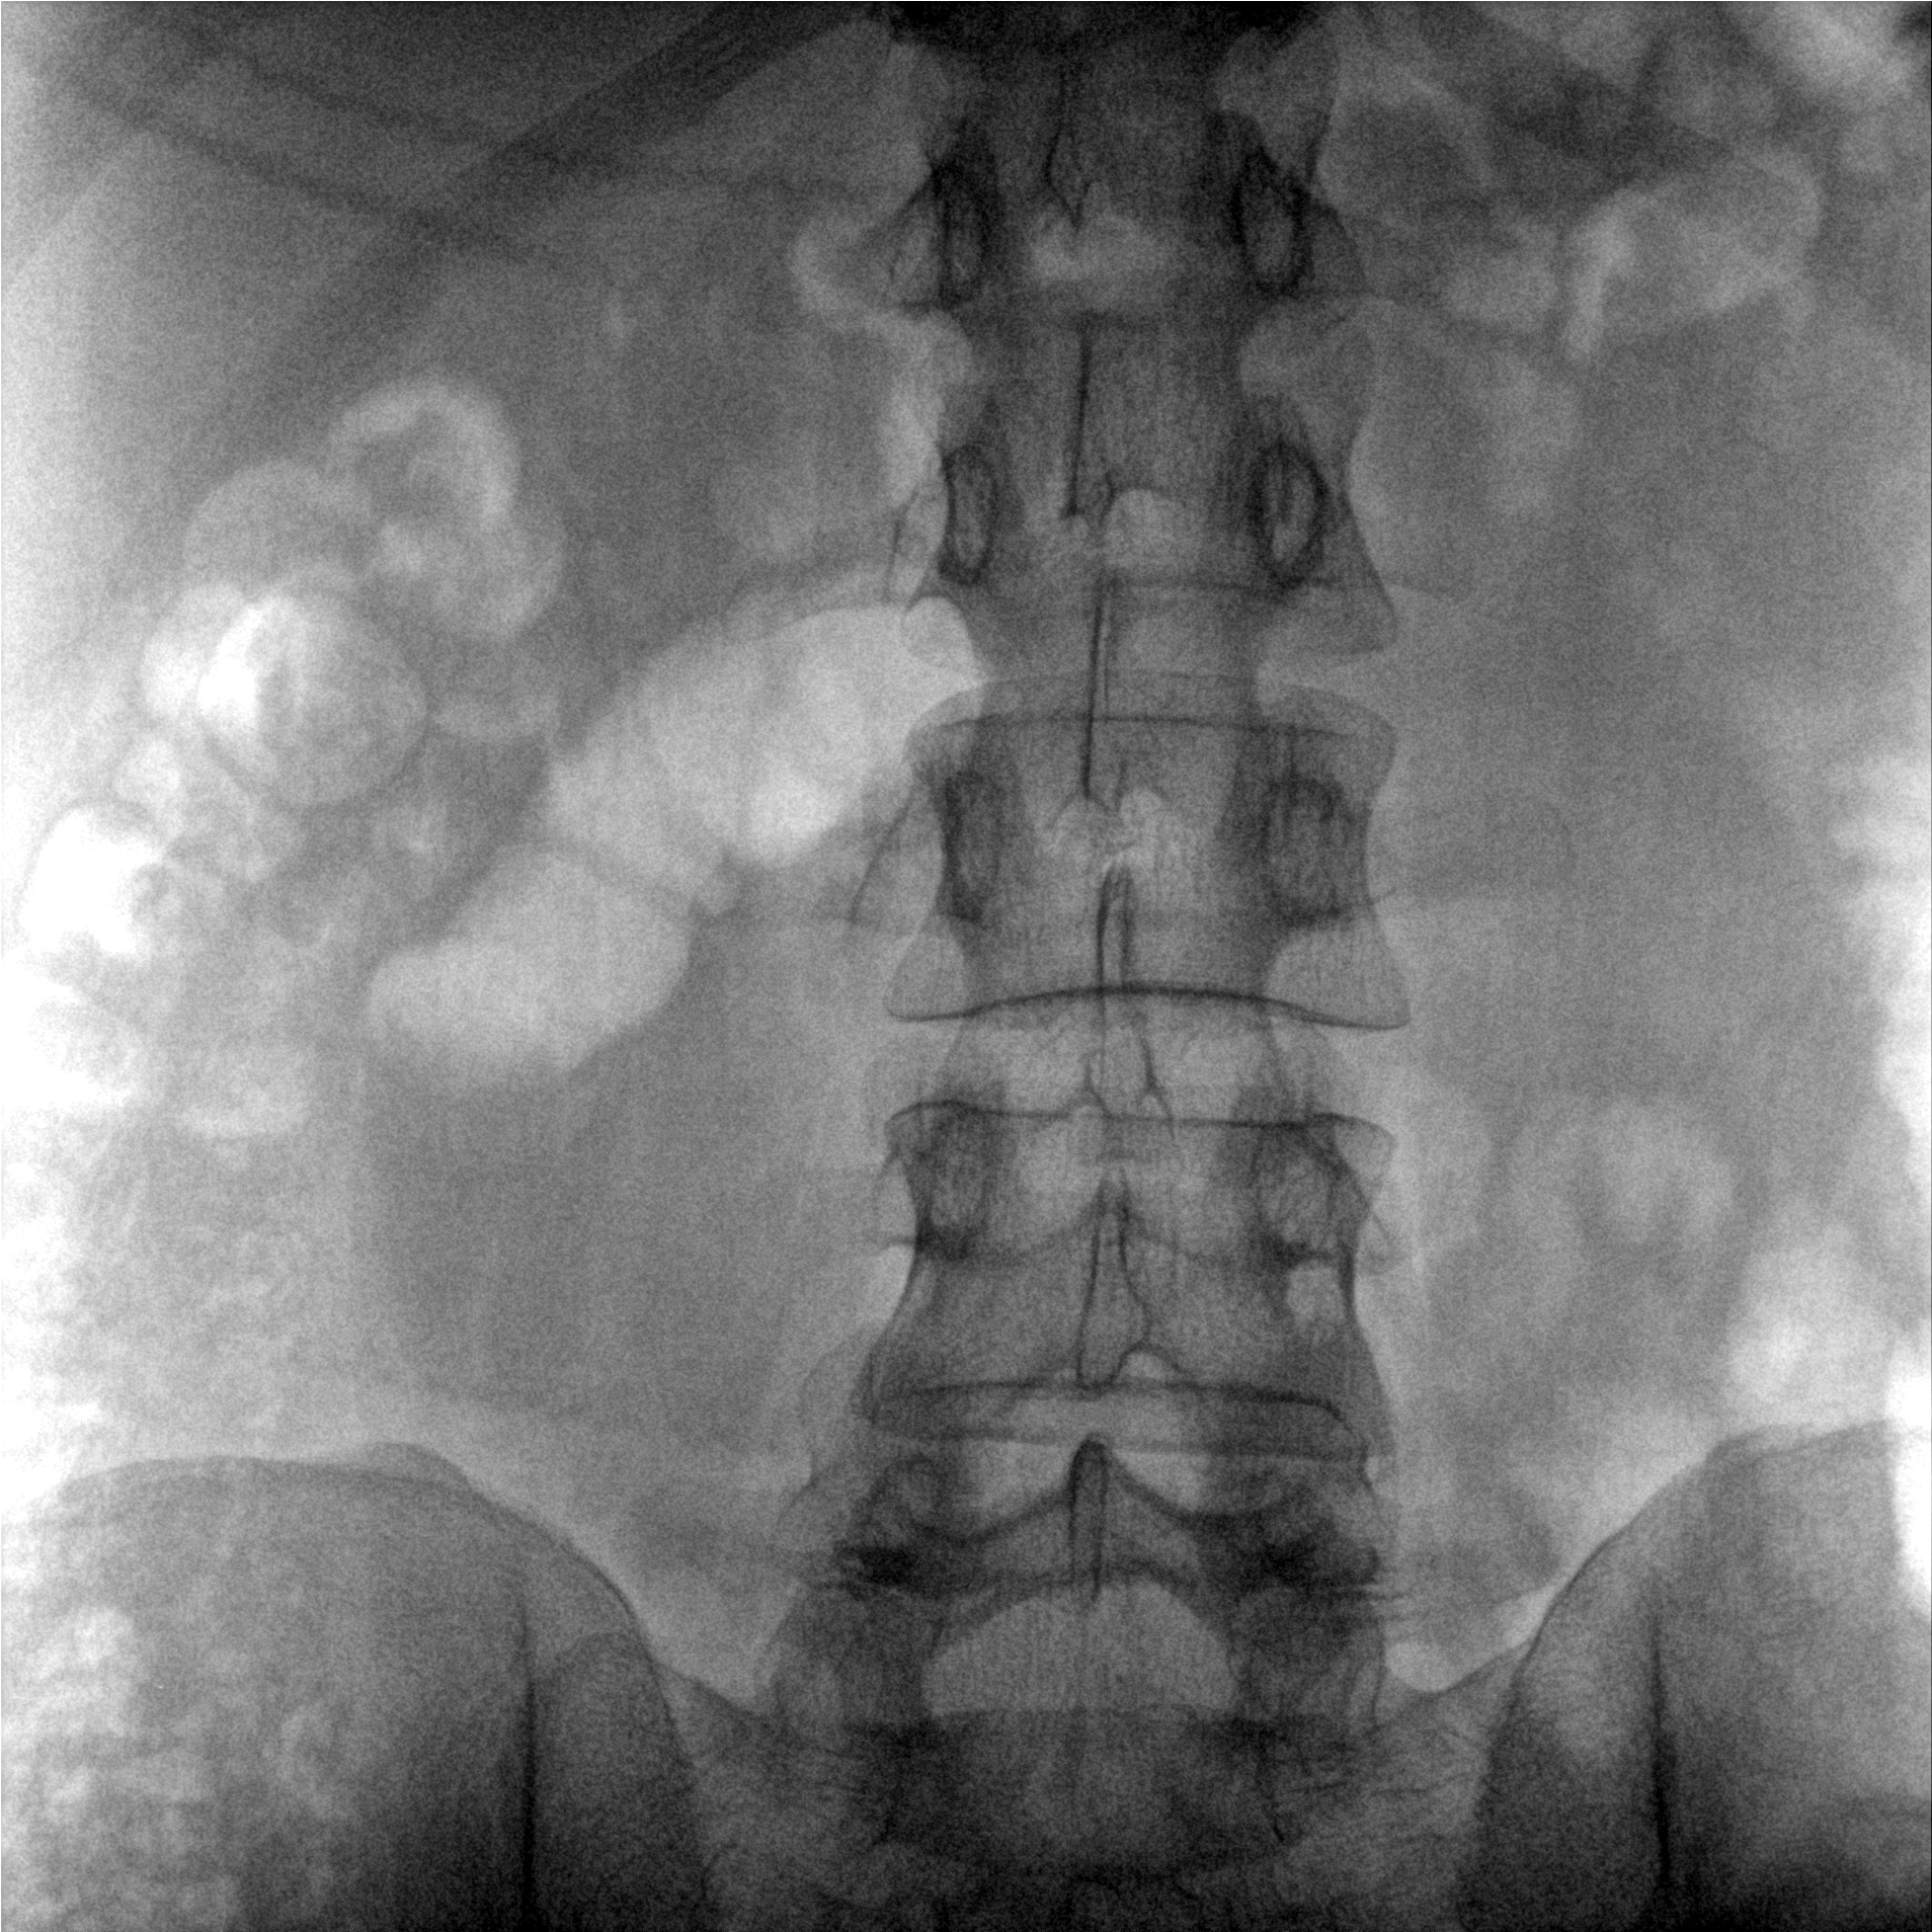

提供更大的術中三維成像視野,采集更多圖像信息,可一次拍全全段頸椎、全段腰椎、七節胸椎、雙側骶髂關節、股骨頭及單側盆骨。

術中三維成像和橫斷面圖像提供多角度的手術診斷信息,輔助醫生進行術中評估判斷,諸如骨折復位情況和內植入螺釘的尺寸和位置,輔助手術更好地完成。